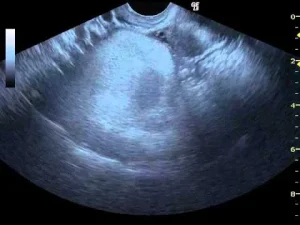

- Görüntüleme Testleri:

- Ultrason: Yumurtalıkların değerlendirilmesinde en sık kullanılan yöntemdir.